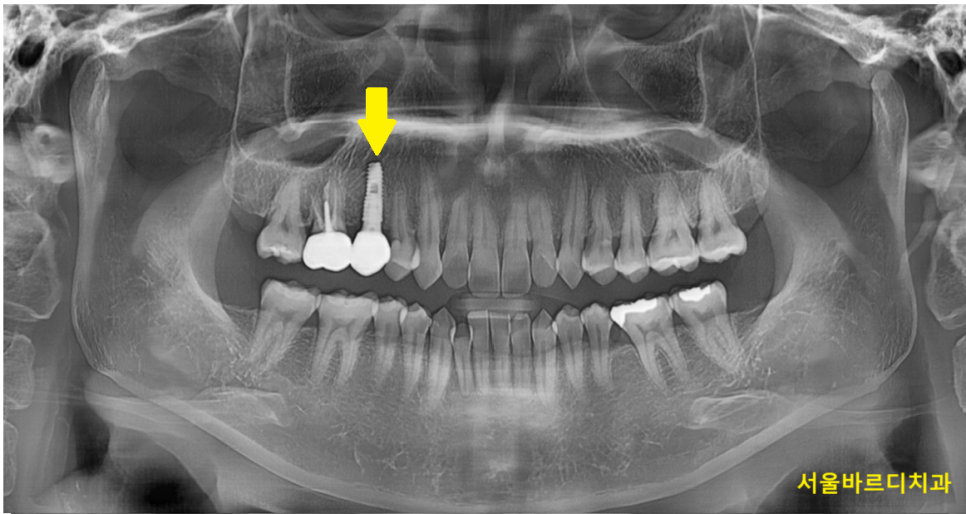

약 두달 뒤 뼈랑 임플란트가 합착이 잘되어서

보철을 만들어 드리고 치료는 종결되었습니다.

오늘은 기존 씌운 치아 부러짐이 발생하여

발치 후 임플란트를 진행한 경우를 보여드렸습니다.